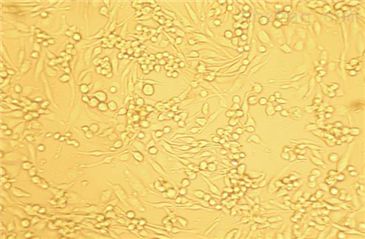

- 生长状态:

贴壁生长

CNE(鼻咽癌细胞)全程提供细胞生物体、生长特性、来源、器官、类型、形态、培养条件、应用、组织、冻存条件等复苏及冻存细胞株说明书信息,专业的技术支持您的细胞系实验,让您实验再无烦扰!培养的前一周内出现质量问题,客户可凭细胞的照片以及书面形式的细胞培养,实验操作过程提供给我司。经技术人员核实认定为可以予以重发的情况,由我司再免费提供一次细胞。